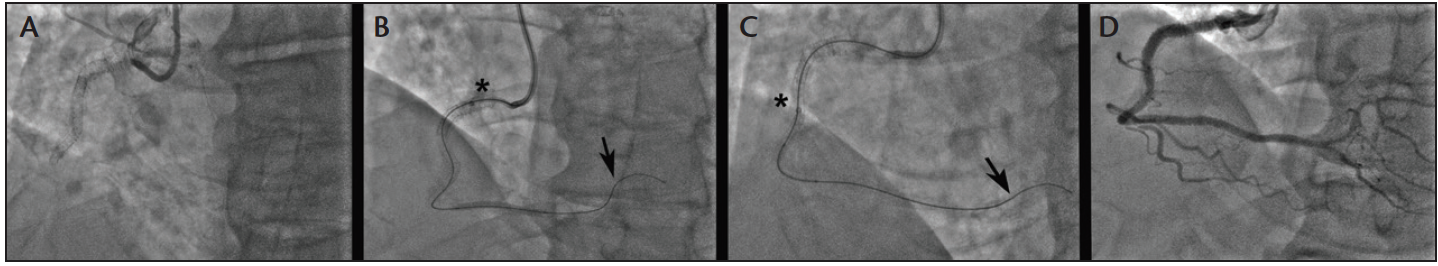

Variations in radial, brachial, and subclavian anatomy can make TR access difficult and remains the most common cause of TR access failure. It is imperative that operators are aware of different anatomic features to anticipate and overcome challenges. Tortuous forearm vessels are often difficult to negotiate with regular wires and catheters. Difficulty advancing wires or catheters is the first sign that either an anatomic variation or radial artery spasm is present, and operators should not persist or exert force that may cause vessel trauma to occur. It is important to inject from the sheath or the catheter to define the anatomy and reduce the risk of complications (Figure 1A and 1B). Most TR access with tortuosity or sharp angulations can be negotiated with a hydrophilic wire to facilitate catheter advancement. Similarly, radioulnar loops (Figure 1C) are a rare occurrence23 that may be negotiated with a hydrophilic guidewire or a standard 0.014-inch coronary wire (BMW Universal, Abbott Vascular), followed by gently advancing a 5-F catheter (Figure 1D). The use of balloon-assisted guide catheter advancement24 over a coronary guidewire (Figure 1E) is able to overcome most cases of radial tortuosity and loops. However, early switching to a femoral approach is advisable if the patient experiences discomfort or spasm.

Figure 1. Challenges in TR access and management strategies. Focal (A) and diffuse (B) radial artery spasm that did not respond to intra-arterial vasodilators. A 360° radial loop (C) that was successfully negotiated with a 5-F catheter over a hydrophilic guidewire (D). A 6-F guide catheter with a 2-mm leading balloon inflated over a coronary wire was used to successfully navigate radial artery tortuosity and spasm (E).